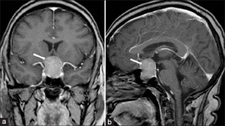

Malign tümörler, kanserli hücrelerin kontrolsüz bir şekilde bölünmesi ve çoğalması sonucu oluşan, çevre dokulara zarar verebilen ve metastaz yapma potansiyeline sahip olan tümörlerdir. Bu tümörler, vücutta çeşitli sistemleri etkileyebilir ve ciddi sağlık sorunlarına yol açabilir. Bu makalede, malign tümörlerin belirtileri, tanı yöntemleri ve tedavi seçenekleri ele alınacaktır. Malign Tümörlerin BelirtileriMalign tümörlerin belirtileri, tümörün türüne, büyüklüğüne ve bulunduğu bölgeye göre değişiklik gösterebilir. Ancak, genel olarak aşağıdaki belirtiler sıkça gözlemlenmektedir:

Bu belirtiler malign tümörlerin varlığını gösterebileceği gibi, başka sağlık sorunlarının belirtisi de olabilir. Bu nedenle, belirtilerin ortaya çıkması durumunda bir sağlık uzmanına başvurulması önemlidir. Malign Tümörlerin Tanı YöntemleriMalign tümörlerin tanısı, çeşitli yöntemler kullanılarak konulmaktadır. Bu yöntemler arasında:

Bu tanı yöntemleri, malign tümörlerin varlığını belirlemek ve tümörün türünü, evresini değerlendirmek amacıyla kullanılmaktadır. Erken tanı, tedavi sürecinde büyük bir öneme sahiptir. Malign Tümörlerin Tedavi SeçenekleriMalign tümörlerin tedavisi, tümörün türüne, evresine ve hastanın genel sağlık durumuna bağlı olarak değişiklik göstermektedir. Başlıca tedavi yöntemleri şunlardır: